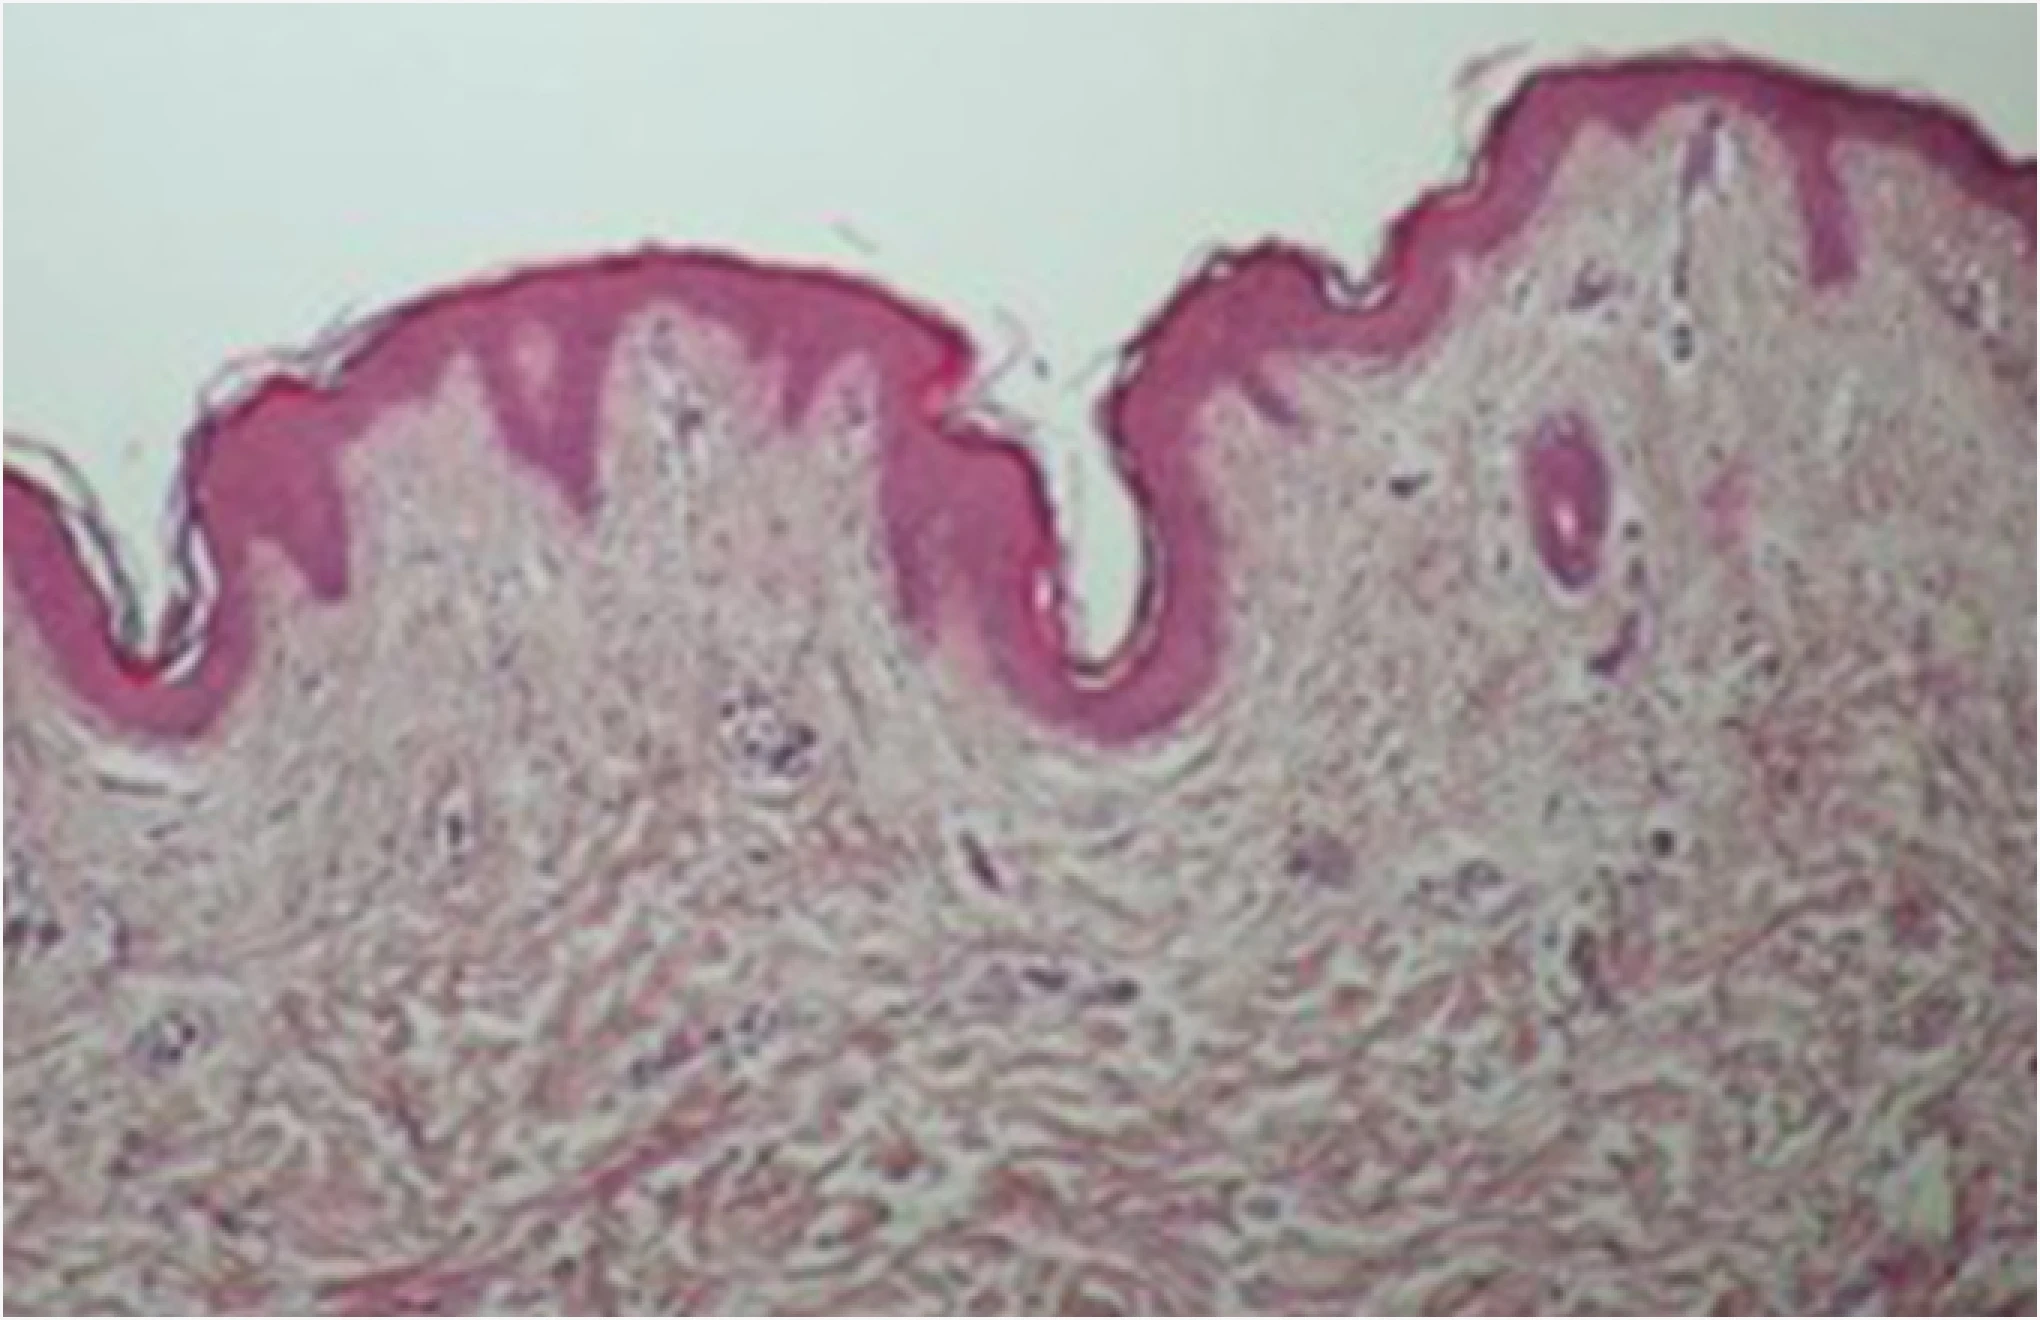

After the ONDA procedure, dermal collagen activation is clearly evident.

As ONDA energy converts to heat, it contracts loosened collagen fibers and triggers remodeling,

delivering both skin tightening and lifting effects simultaneously.